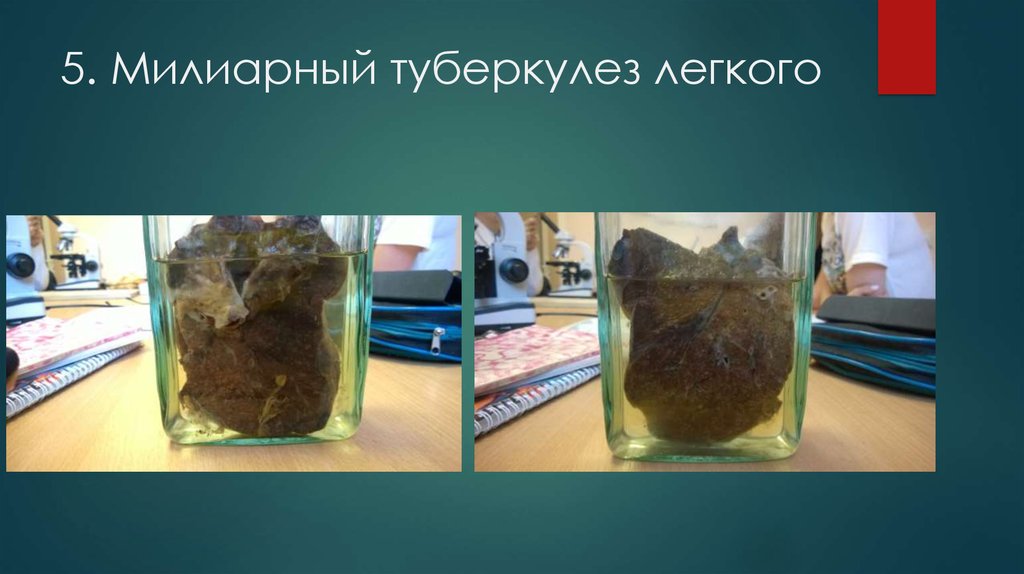

Микроскопический взгляд на мишитарный туберкулез легкого: фотодокументация

Раздел: Снимки-откровения